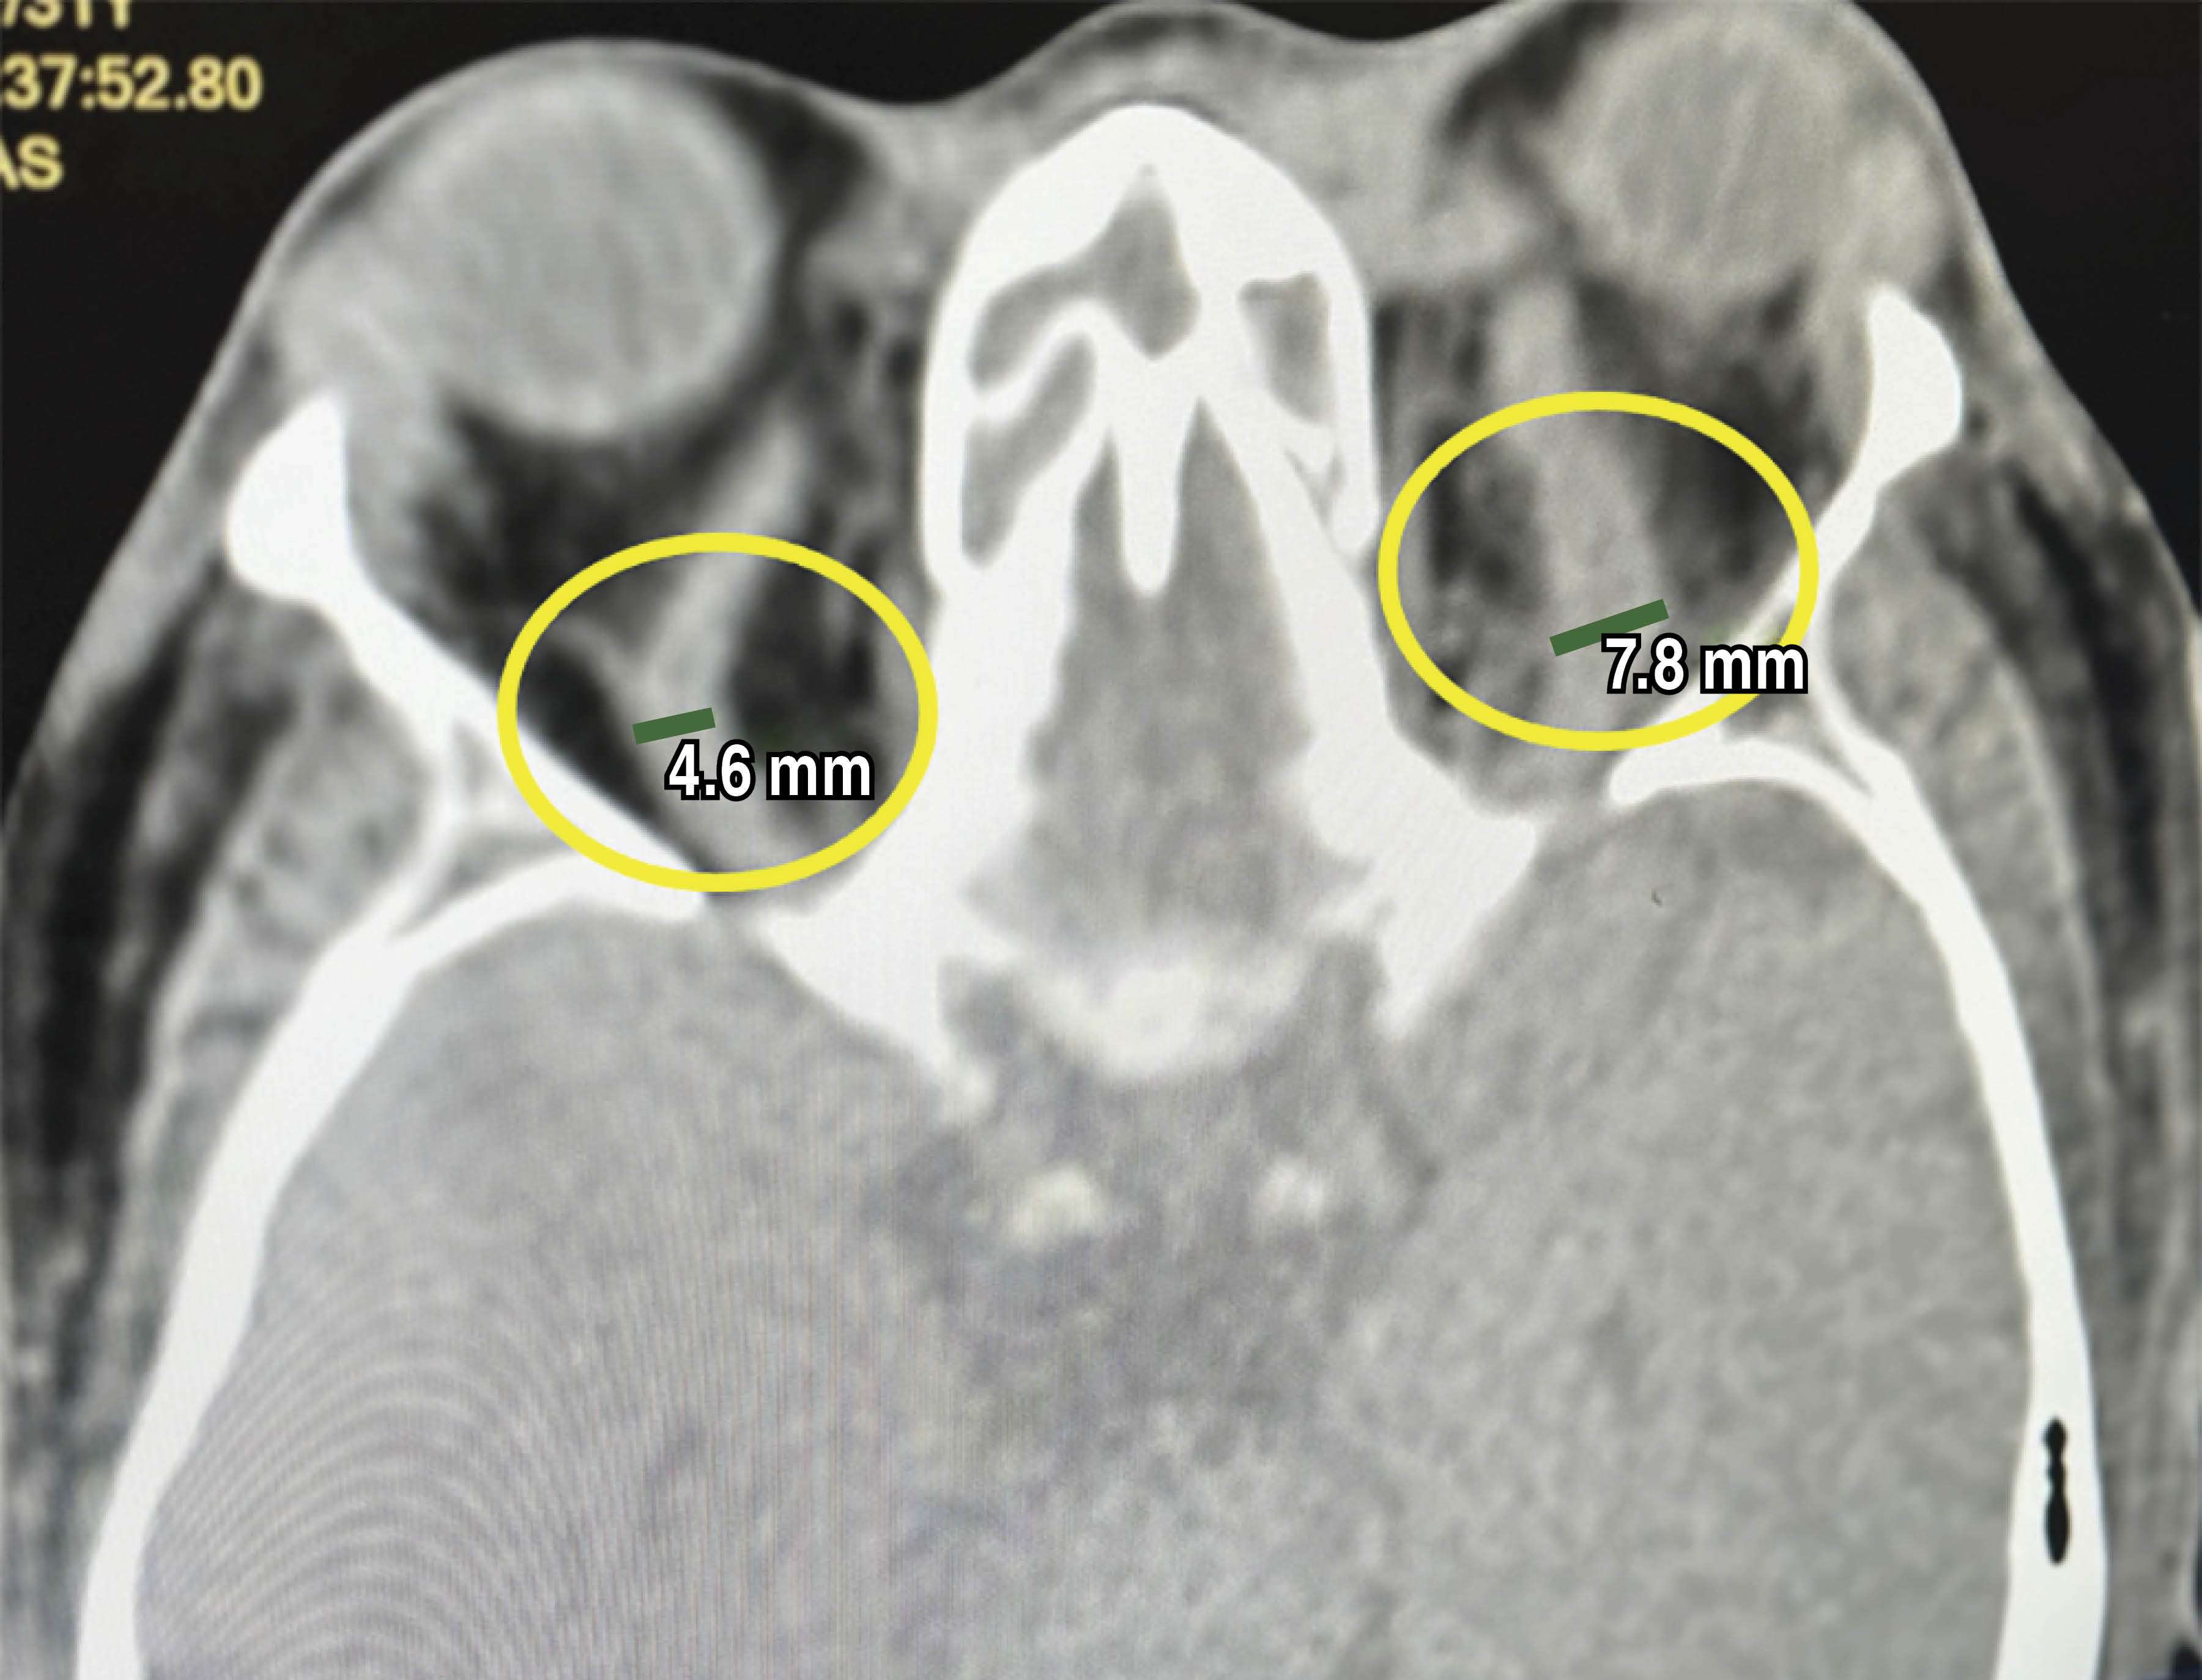

La tomografía axial computada (TAC) orbitaria mostró quemosis, engrosamiento muscular extraocular, proptosis ocular de predominio en ojo izquierdo, celulitis y edema de tejidos blandos, se destaca un aumento de tamaño con relación a las venas oftálmicas derecha de 4.6 mm y la izquierda de 7.2 mm. El parénquima cerebral se encontraba en condiciones normales. Se pudo observar una pansinusitis muy marcada (Figura 2).